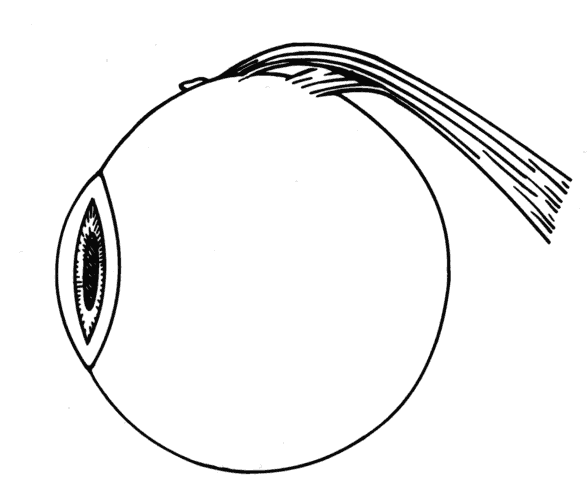

If a rectus muscle has been recessed 5 mm or more, further recession will put the new insertion at or beyond the arc of contact of the rectus muscle and the globe. This may cause decreased function of the muscle and produce noncomitant ocular rotations, especially in extreme gaze positions. To weaken a rectus muscle without disturbing its insertion site, a marginal myotomy can be performed.39,40 Usually, two separate cuts are made into the muscle near the tendon (Fig. 36) until the muscle lengthens. The weakening effect can be graded by increasing the number of cuts from two to three or by increasing the percent of the muscle that is cut. To be effective, a marginal myotomy should be accompanied by resection of the ipsilateral antagonist muscle.

Fig. 36. To perform a marginal myotomy, the muscle tendon is gently stretched between two Jameson muscle hooks. Prophylactic hemostasis is achieved by clamping the muscle or by application of a wet-field cautery to blanch the vessels in the tendon. The muscle is cut with small “snips” using a Wescott scissors.